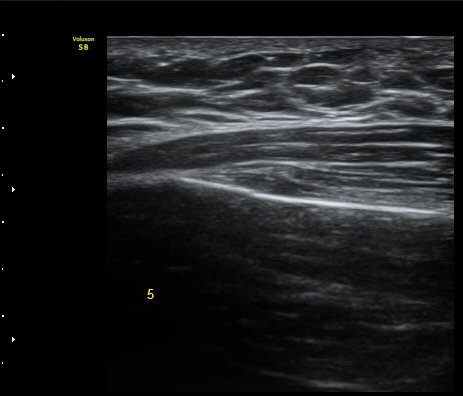

ÇÑ´Þ ÈÄ ÃßÀû°Ë»ç

Á¾´Ü¸é°Ë»ç¿¡¼­ °¡°ñ Çü¼ºÀÌ °üÂûµÊ(formation of callus)   »çÁø 3

°¥ºñ»À Ⱦ´Ü¸é°Ë»ç¿¡¼­ °¡°ñ Çü¼ºÀÌ °üÂûµÊ(formation of callus)  »çÁø 4